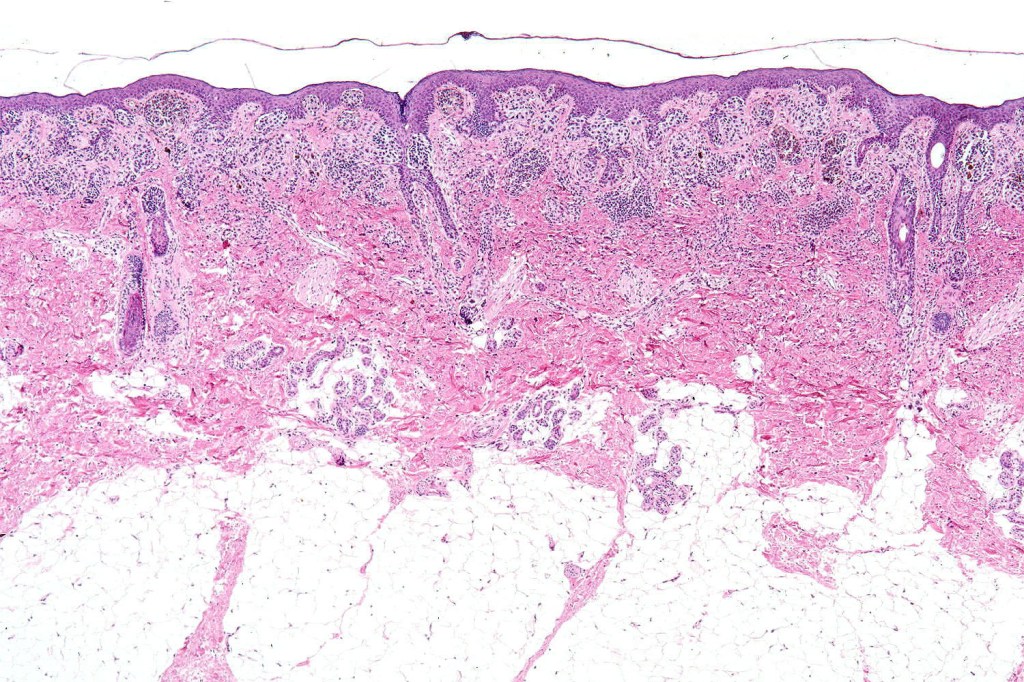

•Most often are distinctive at scanning/low power examination due to the depth of involvement

•Hyperkeratosis, acanthosis and commonly papillomatosis

•Nested junctional component & nests within the papillary dermis

•Diffuse infiltrate of nevus cells often extending deeply into the dermis or beyond, single filing is often present at base & may involve the septa of the subcutaneous fat

•Involvement of appendages & arrector pili muscles

This melanoma arose in a small congenital nevus of the scalp. It metastasized widely. Varying features in different fields.